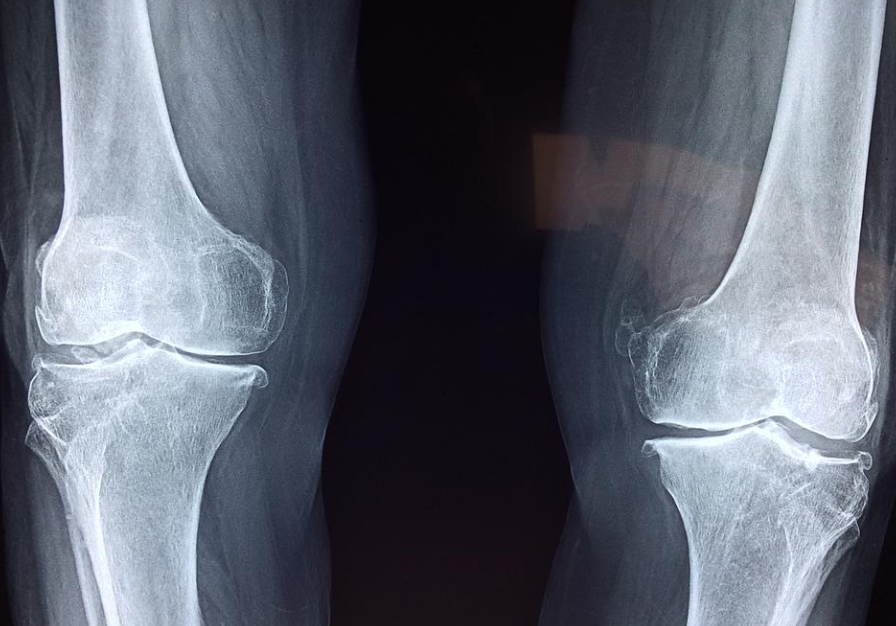

나이가 들면 필연적으로 무릎통증을 호소하는 분들이 많이 계십니다. 연골이 닳기 때문인데, 결국에는 인공관절 수술을 진행하게 됩니다.